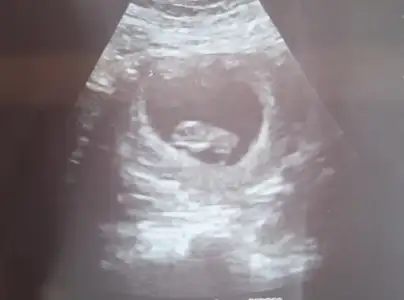

Buraya mesaj attıktan sonra dayanamadım sonunda gittim nöbetçi doktora. 1 hafta geridendi Şuan 2 gün geriden geliyor dedi 10+1 dedi. Ayakları falan hareketliydi çok şükür. Birde burun kemiği organlar vs için 12. Haftada perinatolog

Muayenesi öneririm dedi. Şimdi Anadolu yakasında araştıracağım peritanoloji uzmanı